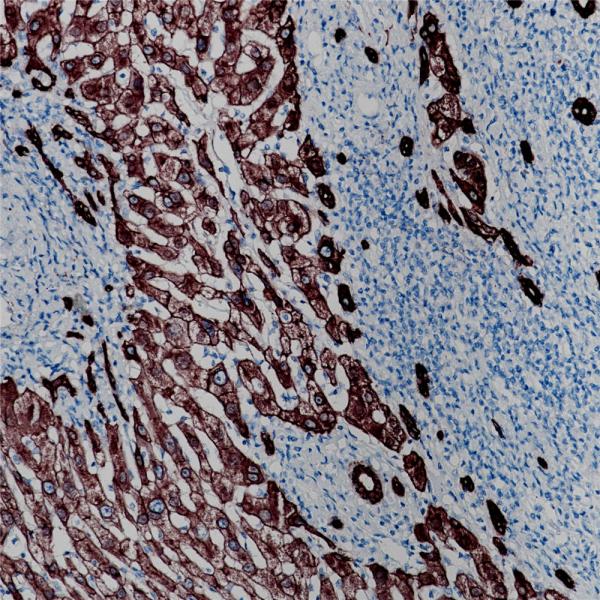

Cytokeratin 8

BP6005